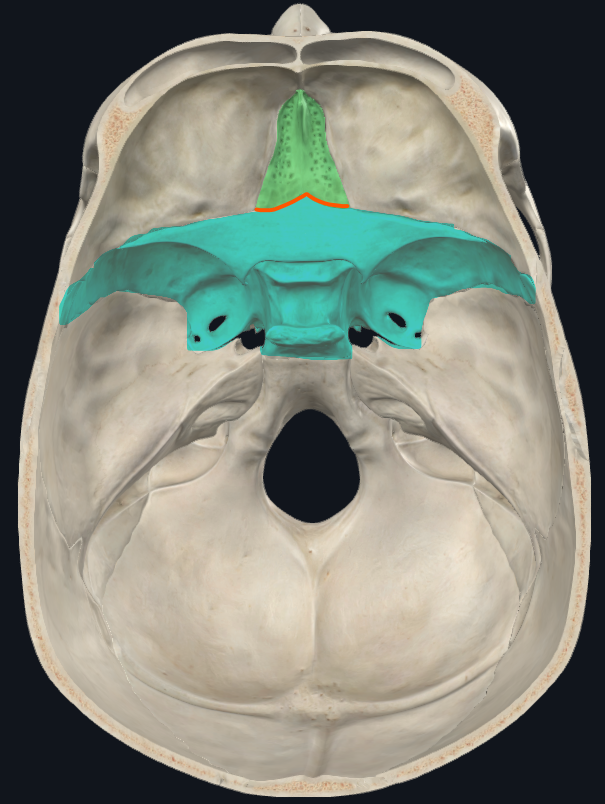

Hueso Etmoides

Parte anterior y media de la base del cráneo

Lámina cribosa del etmoides

Lados se articulan con el frontal

Forma parte del piso de la fosa craneal anterior

Perforada por múltiples orificios, por eso el nombre de cribiforme

Dos apófisis alares que articulan con el frontal, creando el foramen cecum

Apófisis crista galli

Triangular, borde anterior bajo articula con el hueso frontal y completan el agujero ciego(foramen cecum) entre surcos